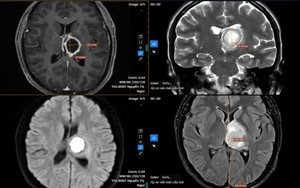

Sống khỏe 2026-03-13T21:00:00Bệnh nhân không ngờ rằng dù chỉ có những triệu chứng đơn giản, chị lại được chẩn đoán mắc một loại nhiễm trùng nguy hiểm trong não.